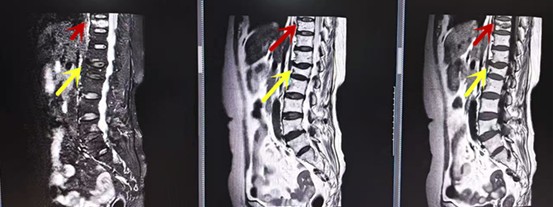

利器三:MRI(核磁共振)

MRI利于磁場和射頻脈沖使體內的氫原子核發生磁共振現象而產生的圖像,對軟組織的分辨率很高,對于脊髓、椎間盤、神經、血管、韌帶、骨髓、腰部肌肉及周圍軟組織有很好的顯示效果,可以清晰的顯示腰椎間盤突出對硬膜囊、神經根壓迫程度,以及骨折是陳舊還是新鮮,同時在脊髓病變(如脊髓損傷、髓內出血或腫瘤)、椎管內膿腫/血腫、椎旁肌肉軟組織病變等方面也具有優勢,但是檢查時間較長,部分患者可能因體內金屬植入物(如心臟起搏器、人工耳蝸等)而無法進行檢查。

箭頭提示腰椎管內腫瘤

紅色箭頭提示新鮮骨折,黃色箭頭提示陳舊性骨折